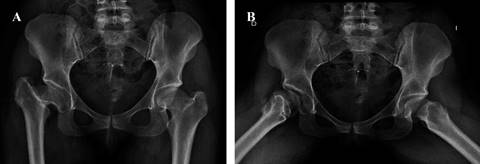

Después de la aprobación del protocolo de estudio por el Comité de Ética de Protocolos de Investigación del hospital y la firma del consentimiento informado, se incluyeron pacientes para cirugía primaria de cadera con antecedentes de DDC tipo I y II de la clasificación de Crowe y secuelas de Perthes de forma prospectiva, entre Enero de 2019 y Marzo de 2020, con un seguimiento mínimo de 24 meses. Se excluyeron pacientes con infección previa, implantes remanentes y fracturas.

La programación prequirúrgica estándar se realizó con radiografías anteroposteriores y axiales de cadera.

Anatomía. La técnica quirúrgica es demandante. Las anomalías acetabulares siempre van acompañadas de una fosa acetabular poco profunda y una pared acetabular deficiente, lo que hace extremadamente difícil para los cirujanos identificar el acetábulo real y colocar la copa en una orientación razonable. Además, existe una alteración en el extremo proximal del fémur.17